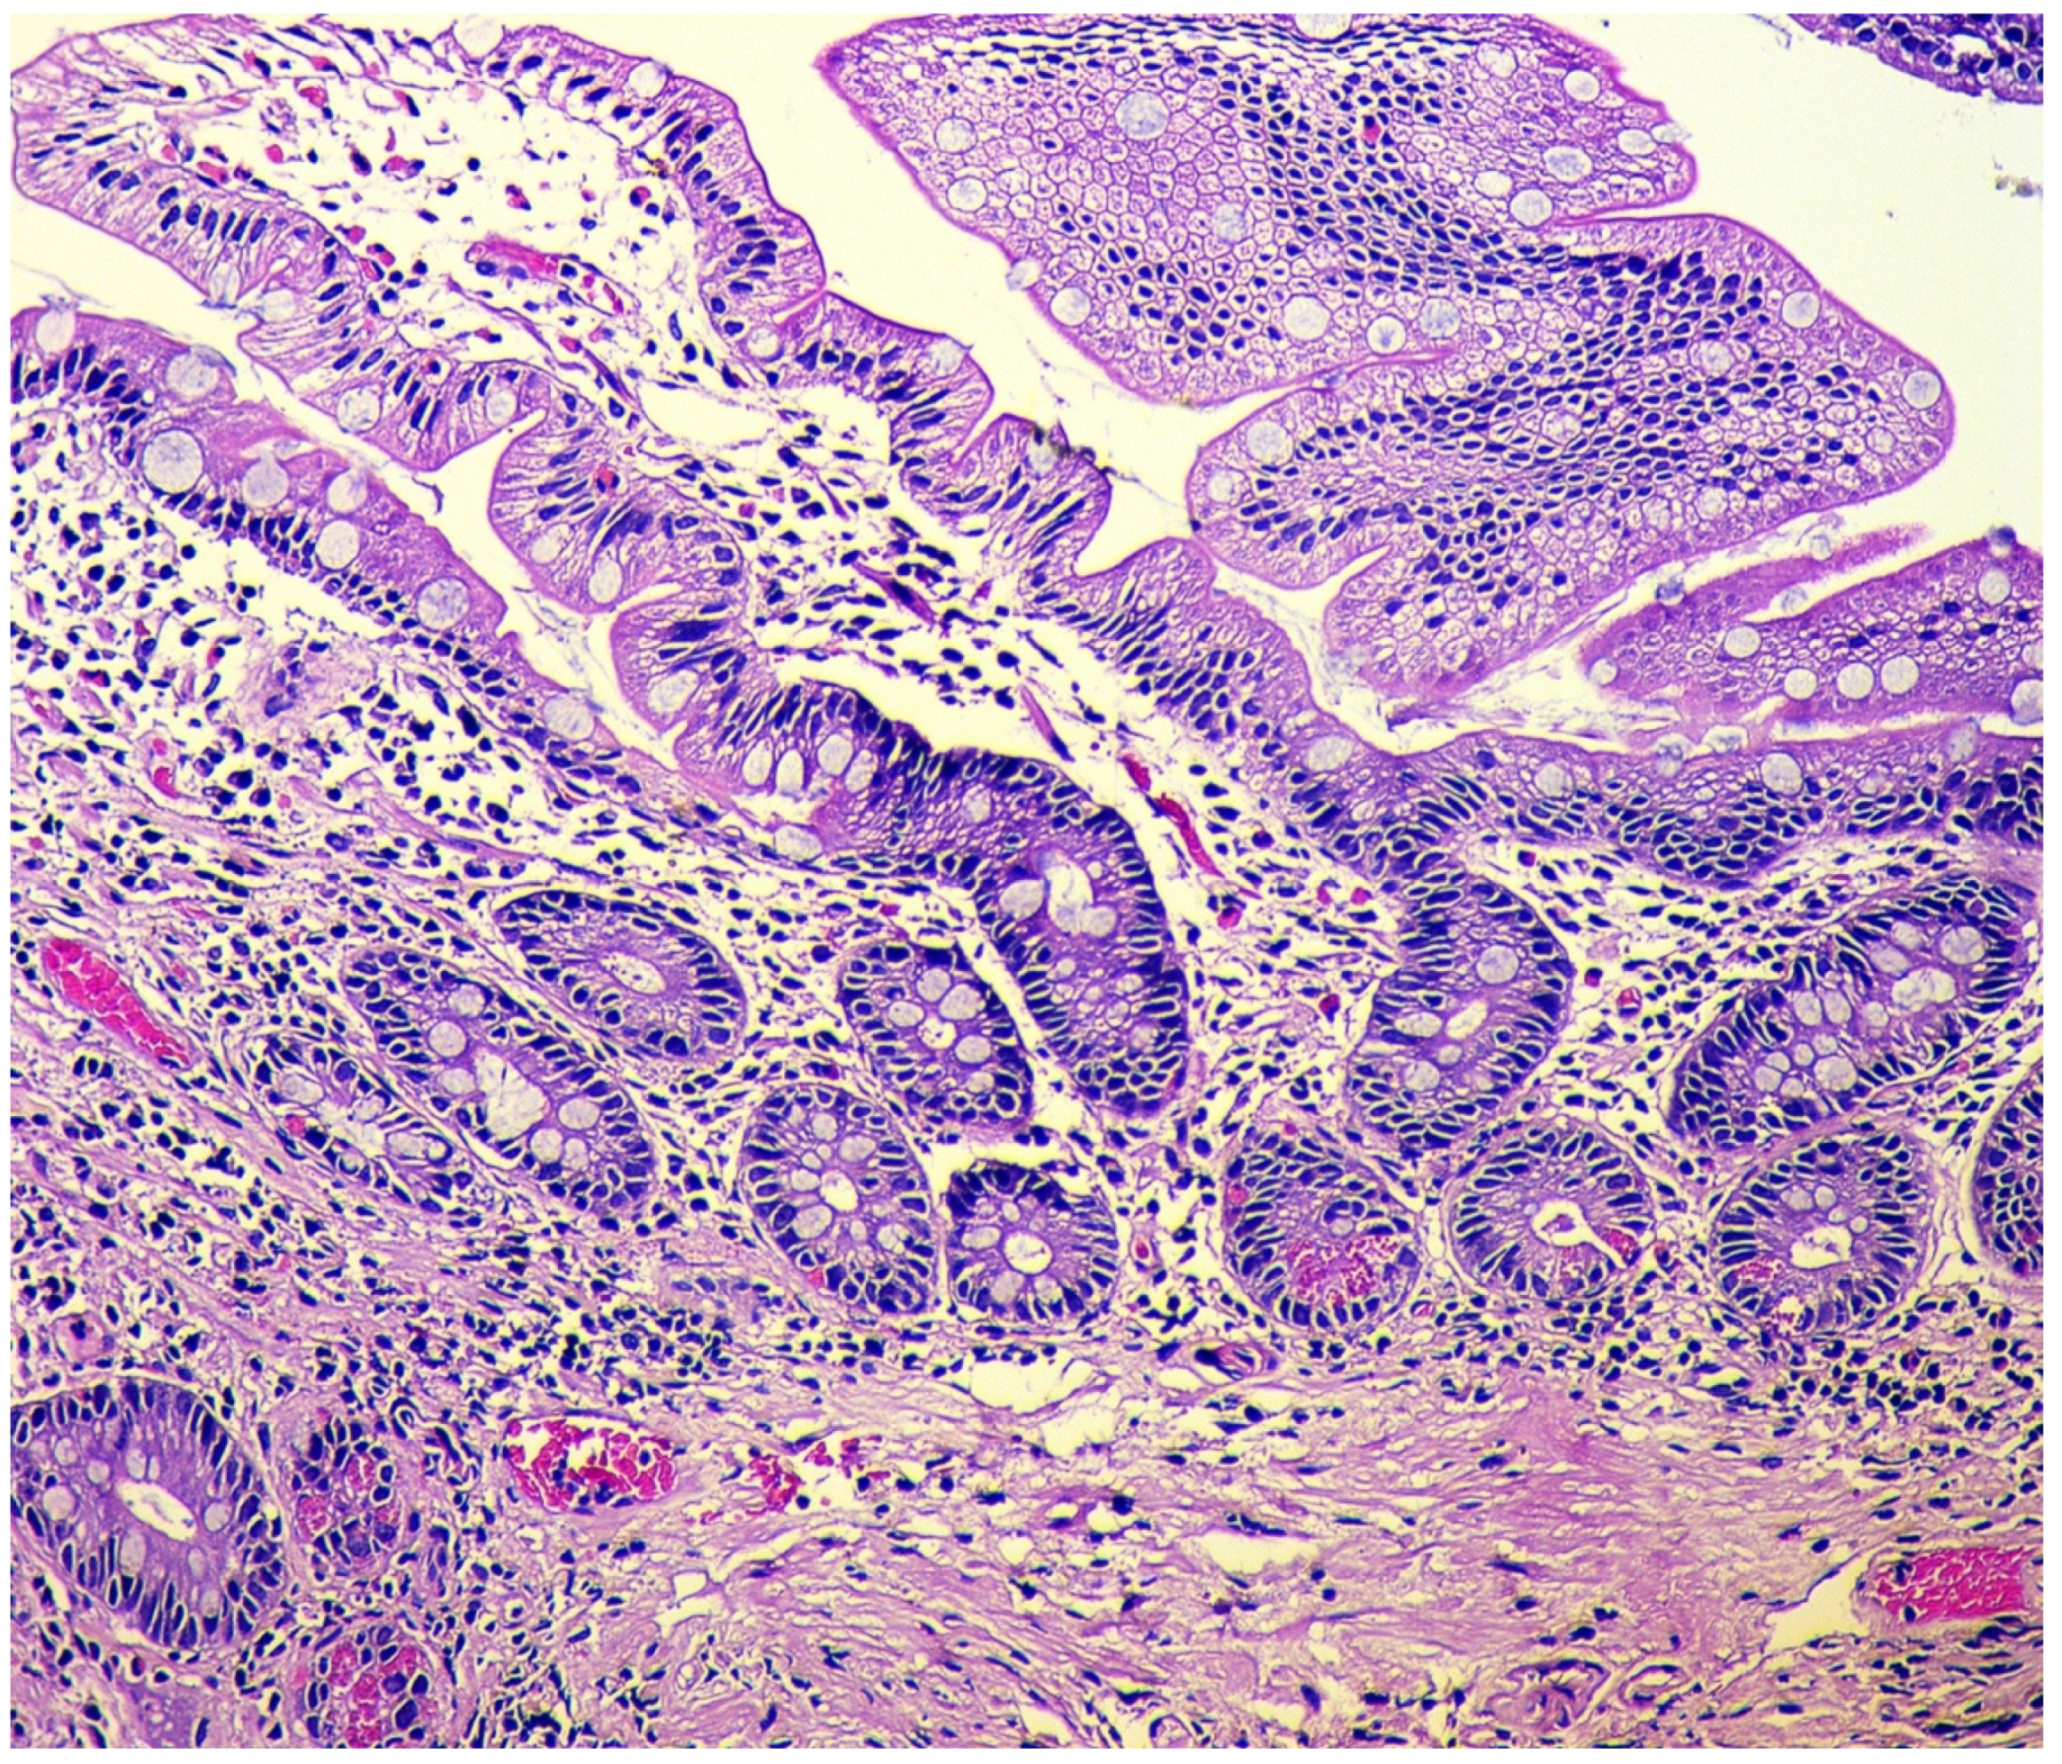

- Simple diffuse hyperplasia. This is characterized by a more than two-fold increase in the population of ECL cells. Diagnosis is difficult due to the lack of clear quantitative criteria. The diagnosis is poorly reproduced on biopsy material.

- Linear hyperplasia. The presence in one visual field of at least two groups of linearly located neuroendocrine cells, consisting of five or more cells. Usually, changes are diagnosed in the area of the neck glands (Figure 4).

- Micronodular hyperplasia. The presence of the cells’ cluster in contact with the basement membrane, but not exceeding the diameter of the gland, up to 150 μm in diameter, or a similar cluster located freely in the lamina propria of the mucous membrane.

- Adenomatous (adenomatoid) hyperplasia. The presence of an aggregate of five or more clusters (Figure 5).